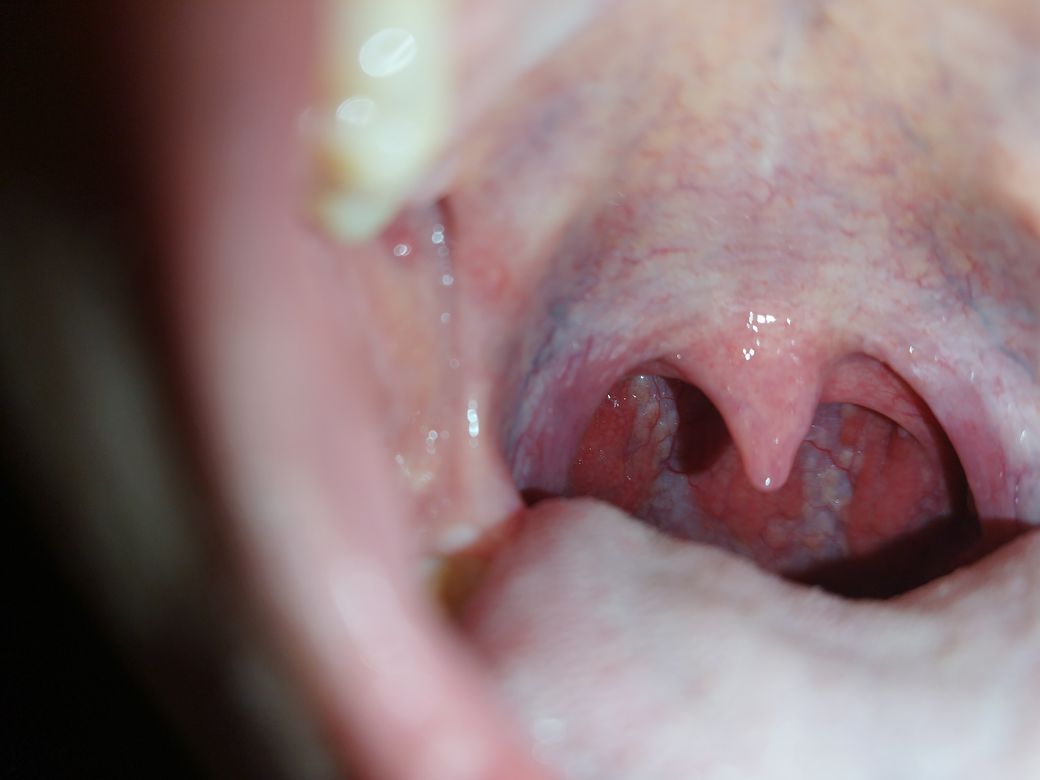

코로나 3일차인데 기침과 목 통증이 너무 심하길래 거울로 봤더니 흰 색으로 움푹 파인? 울룩불룩한? 모습이 보여서 불안하네요... 사진을 찾아봐도 흰 색 없이 빨간 색으로 꽉 차있는 게 정상인 것 같은데... 원래 이런 게 맞을까요?

급성 편도염이 동반되어 있는 양상입니다.

급성편도염은 다양한 원인에 의한 편도의 염증으로, 많은 경우 바이러스나 세균 감염에 의해 발생합니다. 코로나19 역시 급성편도염을 유발할 수 있는 바이러스입니다.